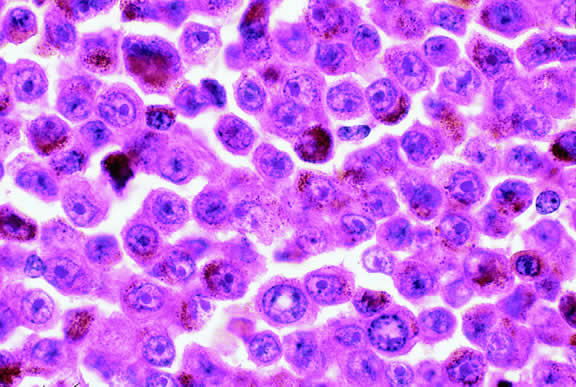

Lymphoma

Although non-Hodgkin's lymphoma often affects the orbit and conjunctiva, intraocular involvement by lymphoma is relatively rare and occurs in two basic ways. First, patients who have widely disseminated systemic lymphoma may develop secondary ocular involvement whose typical manifestation is uveal infiltration. Second, in the variant of central nervous system (CNS) lymphoma that has been called primary lymphoma of the CNS and retina, the vitreous characteristically is involved and the uvea is spared. The latter entity also has been called vitreous large cell lymphoma or ocular “reticulum cell sarcoma.”205–208 In addition to the vitreous, the lymphoma cells also infiltrate the retina, and typically collect between Bruch's membrane and the retinal pigment epithelium, forming solid yellowish RPE detachments, which are highly suggestive of the diagnosis. This rare variant of primary CNS lymphoma should be suspected in older patients who have chronic vitritis that is unresponsive to therapy. Cytologic examination of diagnostic vitrectomy specimens reveals a highly cellular and extensively necrotic infiltrate that contains atypical lymphocytes with prominent nucleoli and protrusions of the nuclear membrane (Fig. 53). The significance of elevated vitreous interleukin 10 levels as a diagnostic marker for lymphoma is controversial.209,210

Fig. 53. Primary central nervous system lymphoma, vitreous. Diagnostic vitrectomy specimen contains large atypical lymphocytes, necrotic lymphoid cells, and nuclear debris. Lymphoma cells in inset have nuclear membrane protrusions and prominent nucleoli. Main figure, Millipore filter. (Hematoxylin-eosin, × 250.)

Many patients who undergo diagnostic vitrectomy to exclude lymphoma actually are found to have a form of granulomatous vitreitis termed idiopathic senile vitritis.211 Cytologically, the latter lacks necrosis and contains a mixture of well-differentiated lymphocytes and epithelioid histiocytes with a spindled or dendritiform configuration. Careful cytologic screening and follow-up are warranted in such cases, however, because vitreous lymphoma occasionally presents with chronic inflammation. Imaging studies and spinal fluid examination should be performed to exclude CNS involvement if vitreous lymphoma is diagnosed.206 CNS lymphoma may produce dementia and other neurologic signs. The prognosis is poor with a mean survival of 22 months. Intraocular Whipple's disease may mimic vitreous lymphoma.212,213